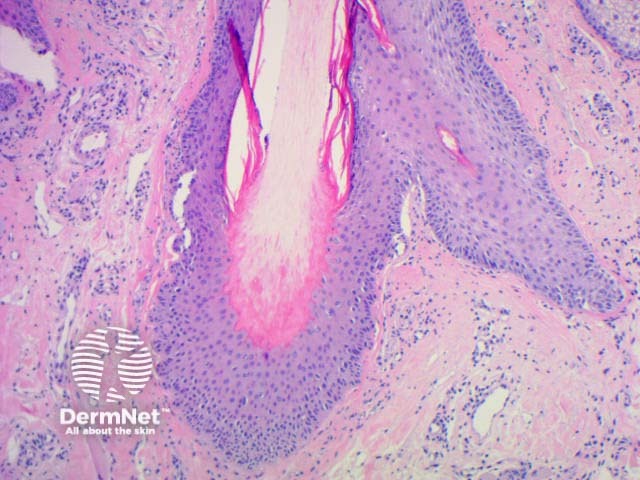

Anagen hairs are fully pigmented and attached to the dermal papilla. They have long, indented roots covered with inner and outer root sheaths.

Hair remains in the telogen resting phase for about 3 months before the follicle enters anagen again. Telogen hairs (also known as club hairs) have short, club-shaped roots that anchor them in the follicle. They lack a root sheath, unlike anagen hairs. The proximal part of the hair shaft is depigmented. Telogen hairs rest in the skin until they are forced out by new anagen hair growing underneath.